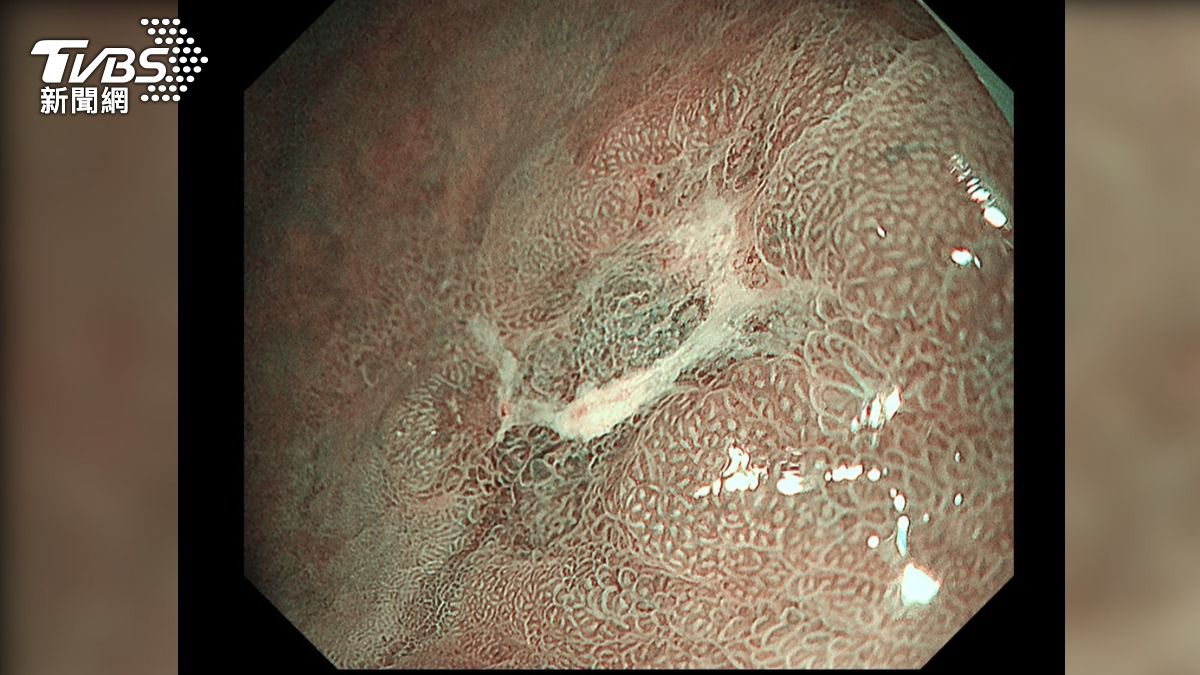

60歲的藝人何篤霖主持節目《命運好好玩》24年,今年卻被目擊到坐著輪椅下機,事後他也公開解釋,是當時膝蓋突然疼痛到無法走路,只好在機場內坐輪椅行動,目前已吃藥緩解。醫師提醒,雖然止痛藥能減輕關節疼痛,但最好還是就醫檢查,避免錯過黃金治療期。